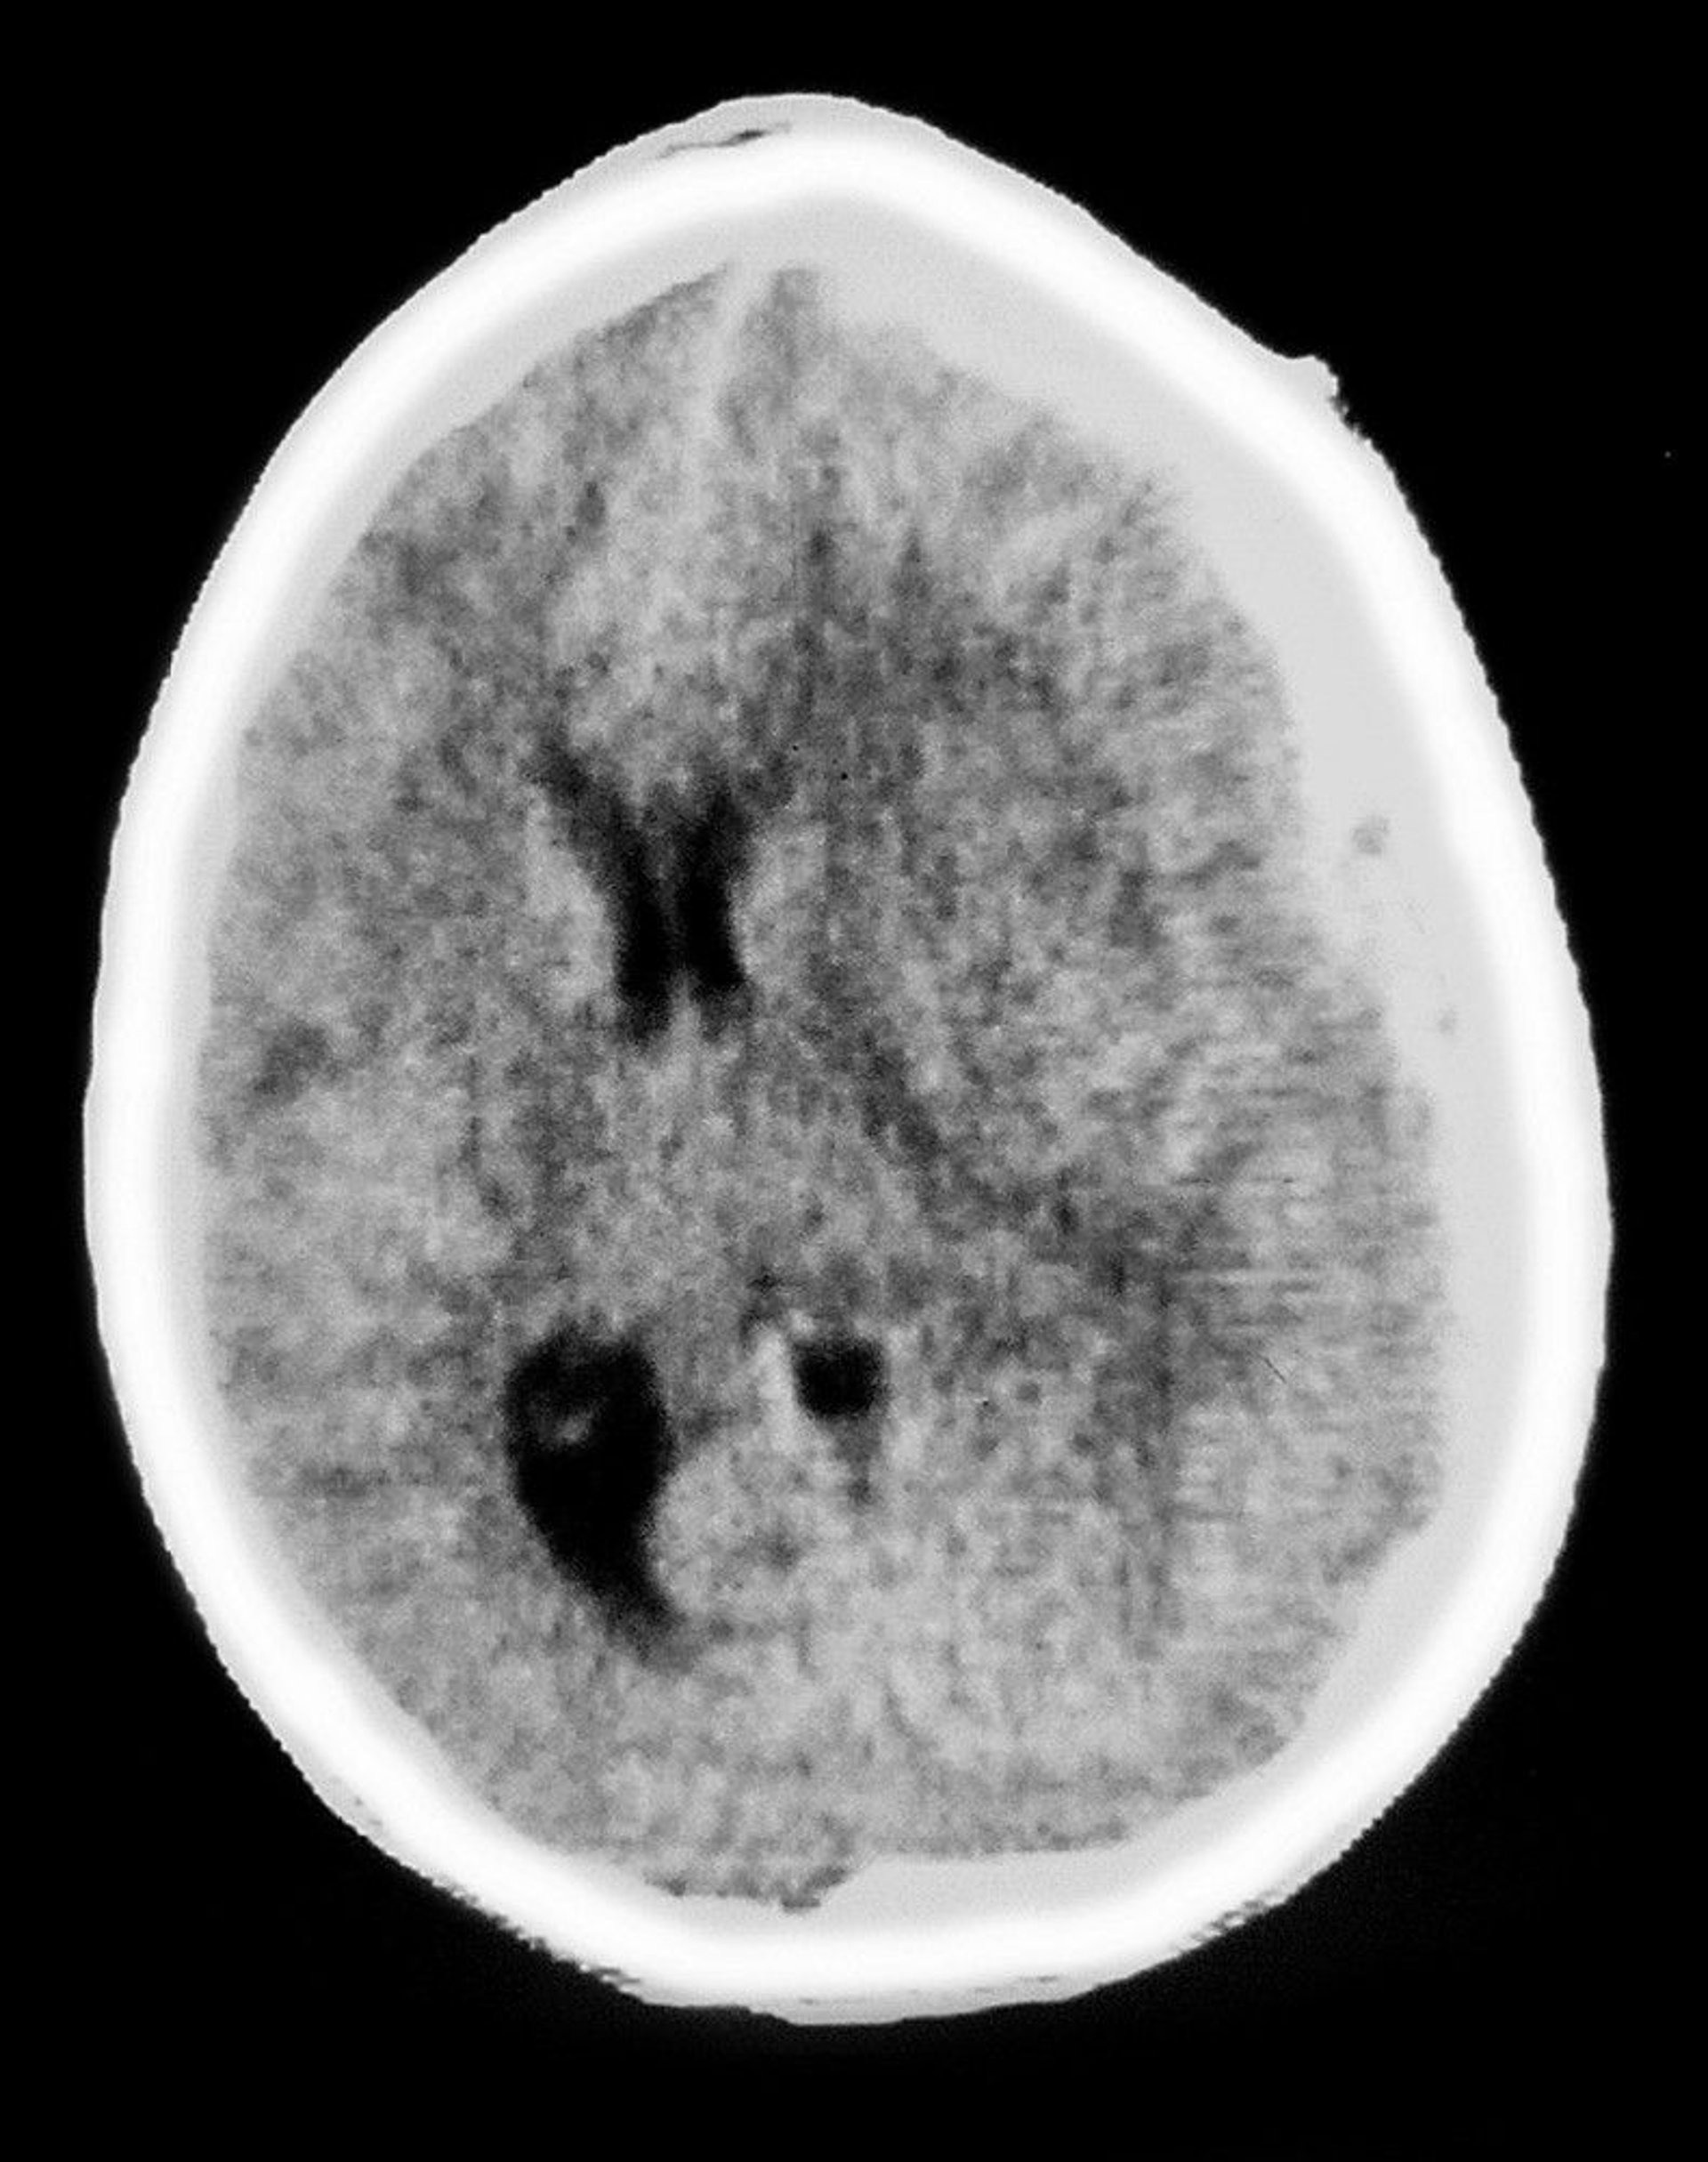

Subdural Hematoma

This CT scan shows a crescent-shaped opacity overlying brain tissue, characteristic of a subdural hematoma. There is also mass effect, with ventricular compression and midline shift.